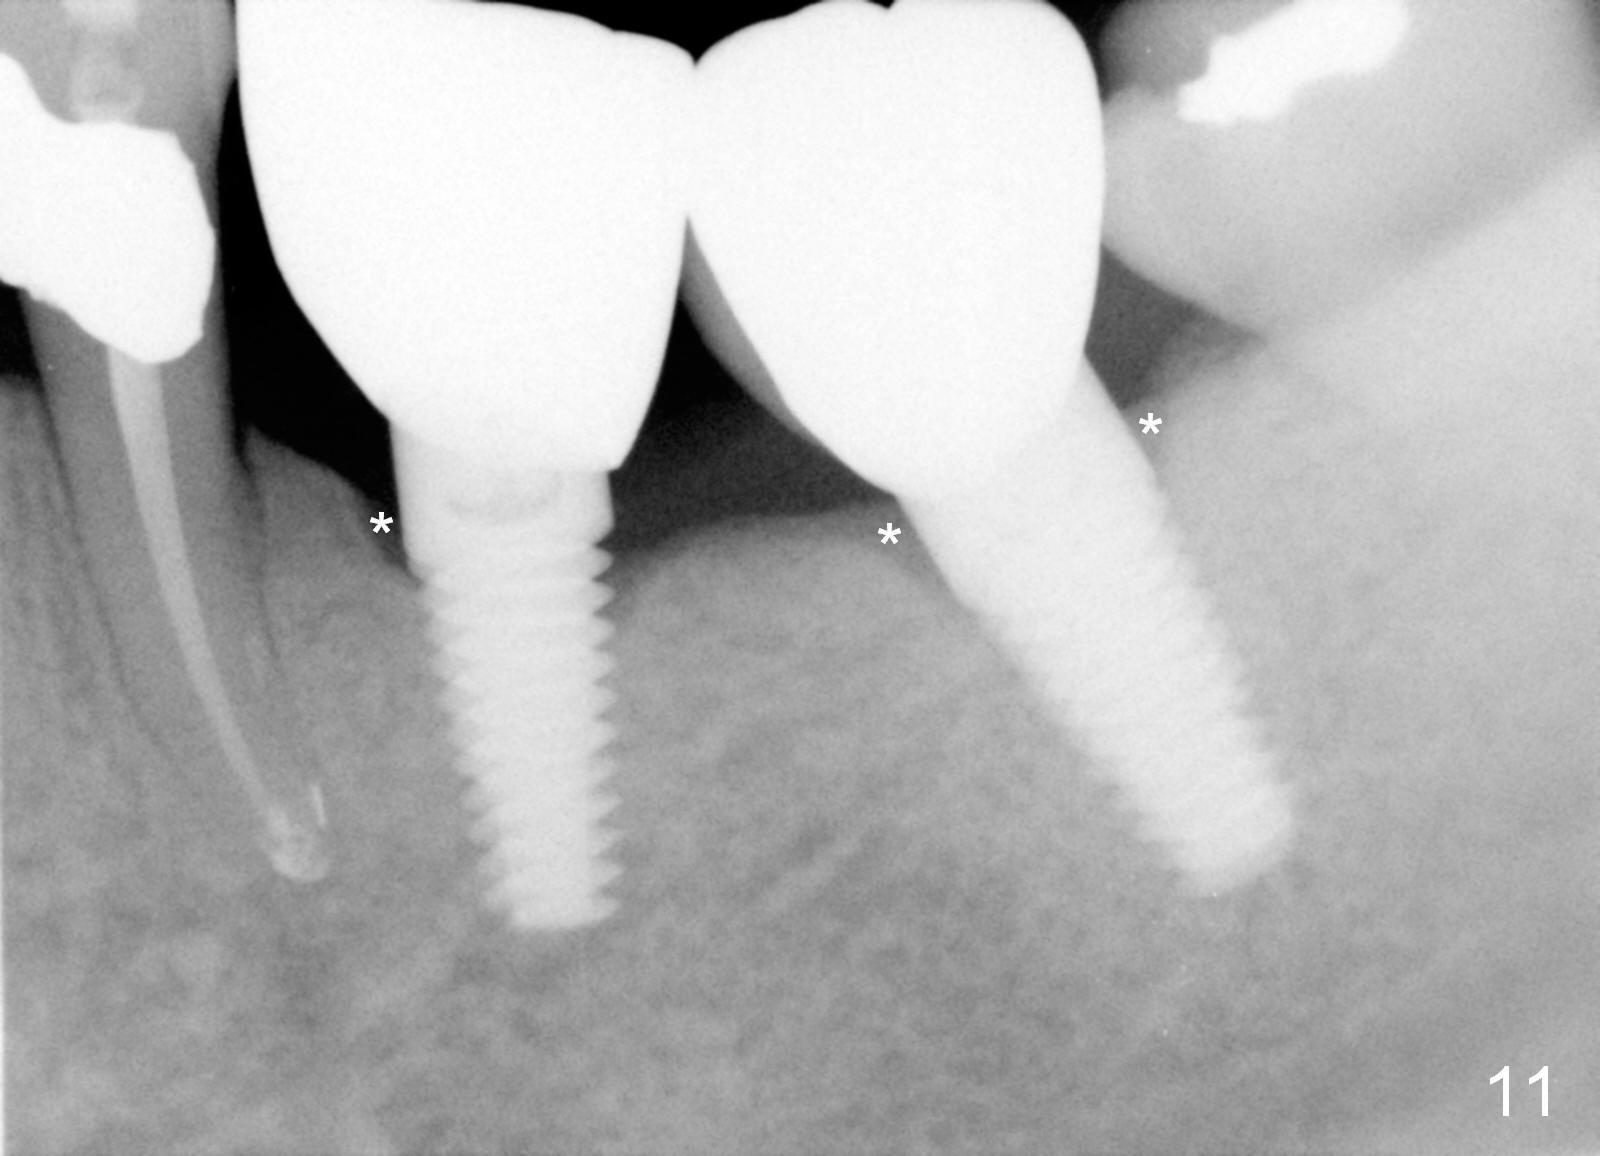

Three months postop, crestal bone has started to resorb (Fig.9 arrowheads).  Resorption gets worse over time (Fig.10: 4 months post cementation, 11 months postop) (Fig.11: 1 year 2 month post cementation).  On the other side (#30), postop bone resorption is not so severe.  The patient's main concern is that she does not have normal taste ever since she got the implants.